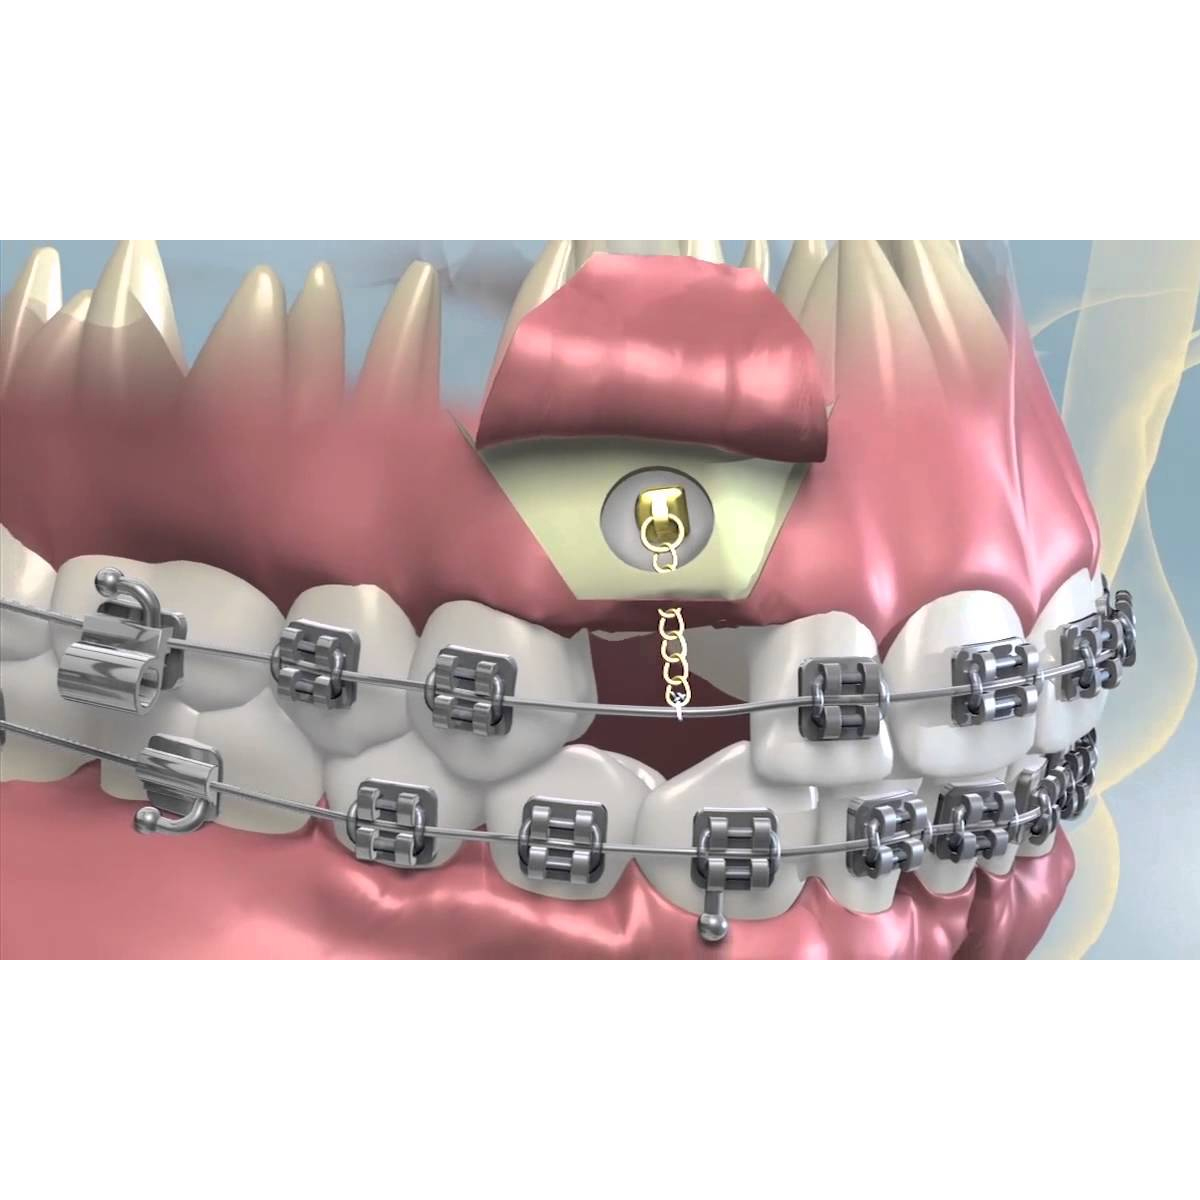

- Lingual Bondable Buttons with Chain: These buttons come with a built-in chain attachment. They are convenient for connecting to various orthodontic accessories, such as elastics or power chains.

- Attachment of Accessories: Depending on the treatment goals, orthodontic accessories such as elastics, power chains, or archwires are attached to the Bondable Buttons.

- Alignment and Straightening: They help secure archwires in place, guiding teeth into their desired positions and ensuring proper alignment.

- Elastic Placement: Bondable Buttons serve as anchor points for elastics, allowing orthodontists to apply forces to correct bite issues, close gaps, or achieve specific tooth movements.

A: Bondable Buttons serve as anchor points for elastics. These elastics are used to apply specific forces to correct bite issues, close gaps between teeth, or achieve precise tooth movements. The buttons ensure that the forces are applied accurately.